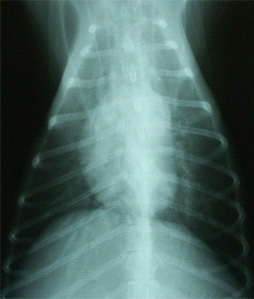

雑種犬、13歳、オス。体重10.6kg。3日間の咳のあと突然呼吸促迫症状。白血球数 40900/μl、胸部X線にてびまん性肺胞浸潤影(図1)、心エコーにて左房拡張・MRなし、血液ガス分析にてpHa 7.50, Paco2 23 mmHg, Pao2 44 mmHg, AaDo2 78 mmHg, Pao2/FIo2=210で重度な低酸素血症を伴った慢性呼吸性アルカローシスを示した。非心原性肺水腫 (Acute Lung Injury)と診断した。治療開始から、酸素室、フロセミド、メチルプレドニゾロンを投与したが8時間を経過しても依然としてPao2 46 mmHgおよび胸部肺胞浸潤影あり改善みられず、スパンカー®(パーカッションネア・ジャパン株式会社、東京)を用いたIPV療法を試みた(図2)。3日間続け、Pao2 94 mmHgと正常化し、びまん性肺胞浸潤影もほぼ消失し(図3)、全身状態も改善し退院となった。3週間後、気管支鏡検査により好酸球性肺炎であることが判明した。

図1 症例1の初診時胸部X線所見。両側性肺胞浸潤影あり。